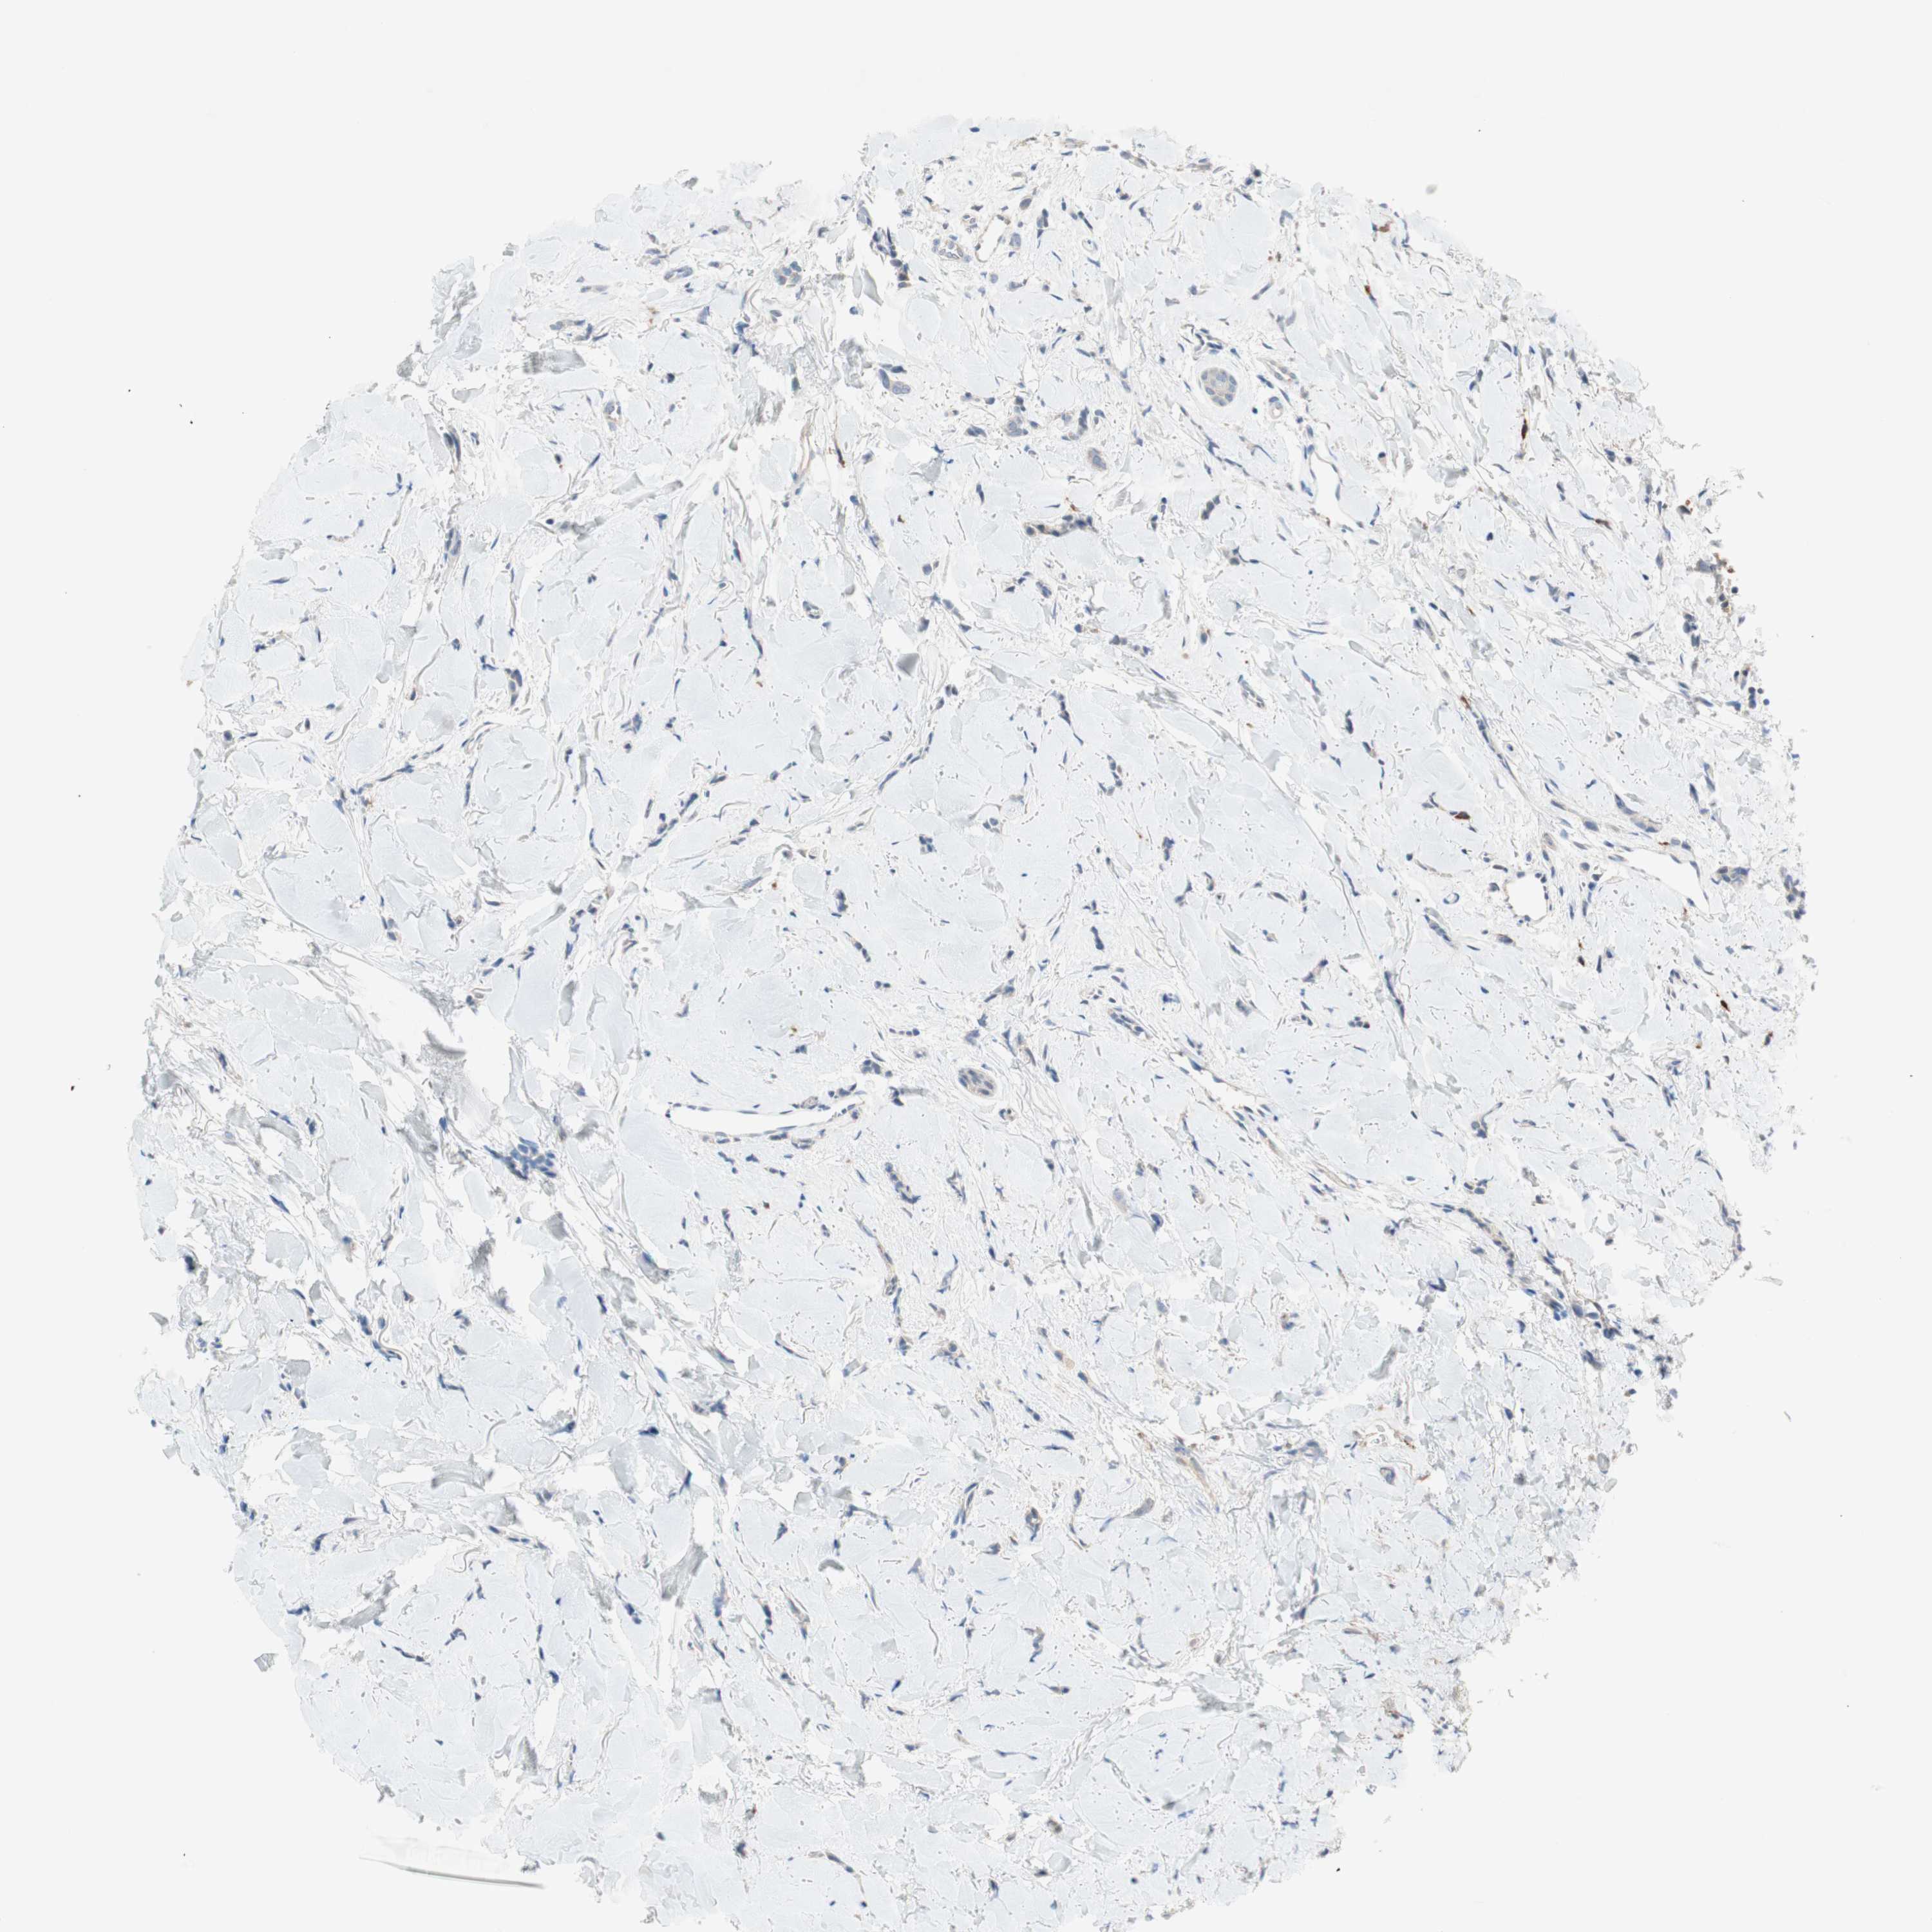

CANCER BREAST CANCER Show tissue menu

BRCA TCGA BRCA VALIDATION PROTEIN EXPRESSION